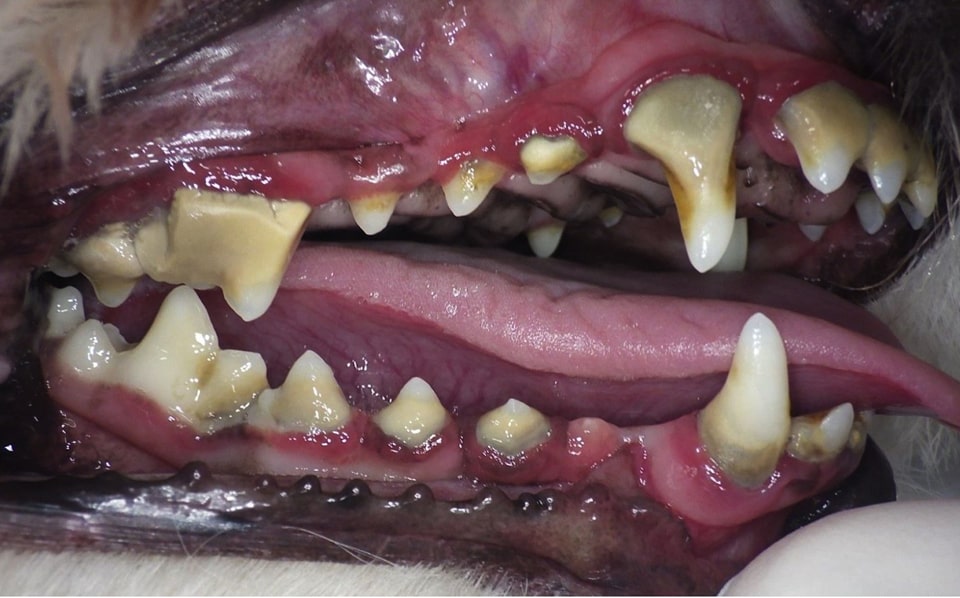

重度歯周病

処置前